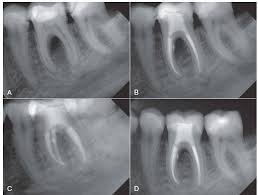

Chụp phim răng cận chóp theo nguyên tắc song song là phương pháp chụp phim răng miệng phổ biến nhất trong nha khoa. Nguyên tắc của phương pháp này là sử dụng tia X để chụp ảnh răng miệng của bệnh nhân bằng cách đặt máy chụp ở một khoảng cách cố định với răng miệng và đưa tia X phát ra về hướng song song với đường trục của răng. Khi tia X đi qua răng miệng, các tia X sẽ được hấp thụ bởi các cấu trúc răng miệng khác nhau và điều này sẽ tạo ra một hình ảnh của răng miệng trên màng phim.

Chụp phim răng cận chóp theo nguyên tắc song song

Hình ảnh minh họa